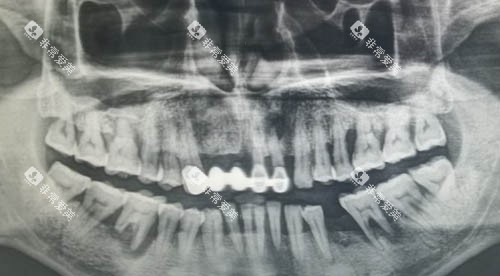

除了实验室测试,临床术例也是评估种植牙质量的重要依据。

从一些口腔医院的反馈来看,韩国登腾经过多年的临床应用,积累了大量成功术例,医生对其操作也较为熟练。

而利多齿作为国产新兴品牌,近年来也有不少成功的种植术例。

许多患者在使用利多齿种植牙后,反映咀嚼功能修养良好,没有出现明显的不适或并发症。